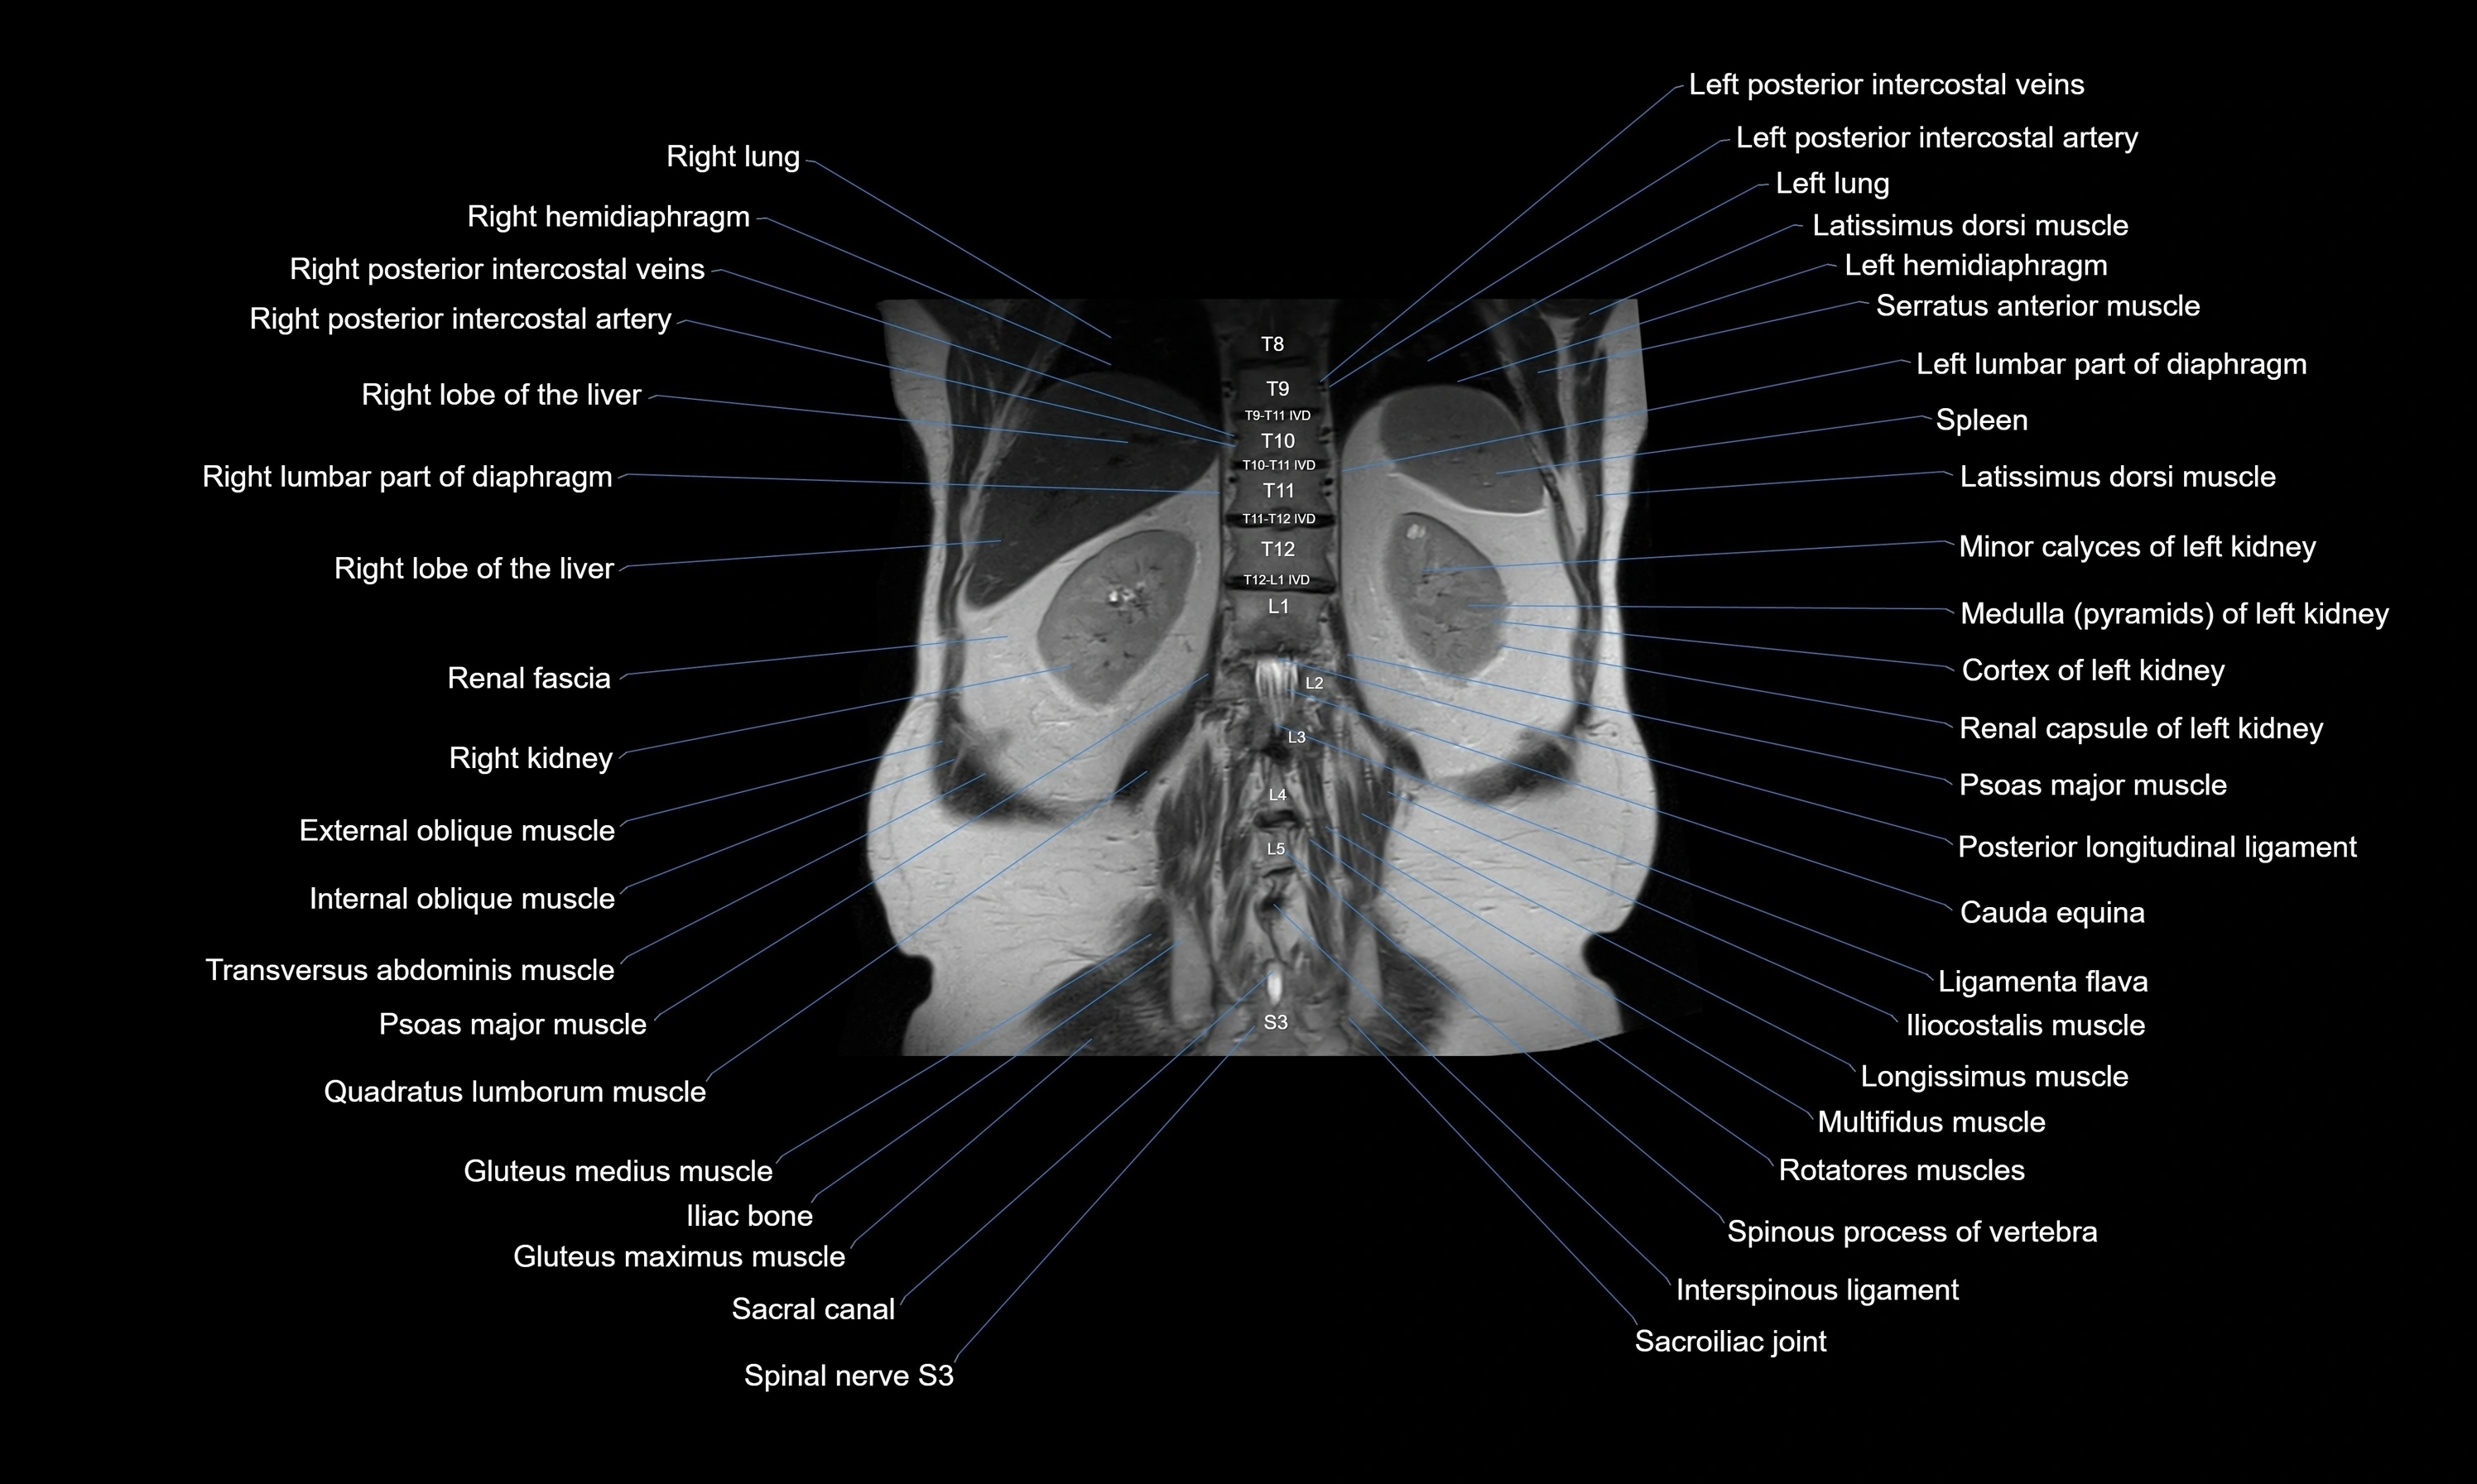

MRI images